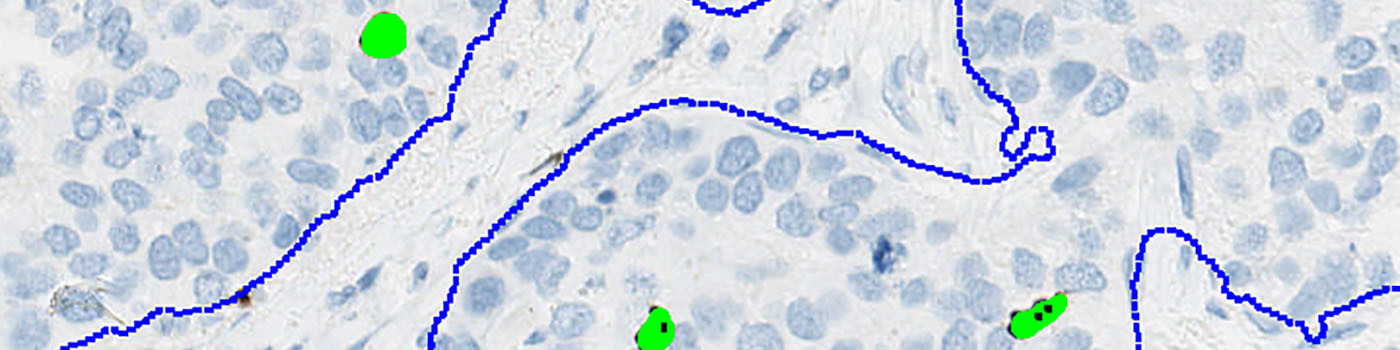

Two serial sections stained respectively for PHH3 and Pancytokeratin (PCK) must be used in this APP. Tumor regions are identified automatically on the PCK stained slide and the outlined tumor region is overlaid on the PHH3 stained slide, thus automatically identifying tumor regions.

Second, tumor areas are automatically detected from the PCK slide and outlined as regions of interest (ROIs) (see FIGURE 4). The ROIs are then superimposed on the aligned PHH3 tissue slide to outline the tumor region for subsequent analysis limited to the inside of the tumor regions (see FIGURE 5).

PCK is used as a cytoplasmatic marker to localize the cancer tissue.

To employ the VDS approach for PHH3, two serial sections must be stained for PHH3 and PCK respectively.